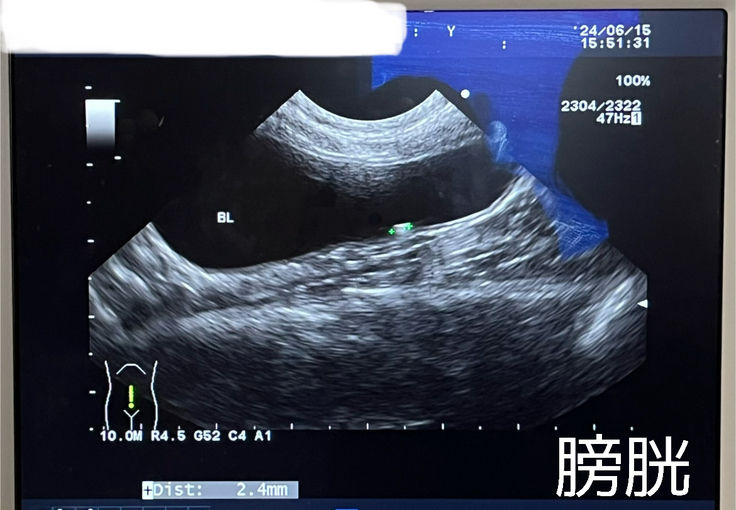

膀胱に2.4mmの結石ありました。

尿管にあった2mmの結石が見つからなかったので、膀胱へ降りてきたのかもとの事でした。

膀胱で詰まってしまう可能性があるため、排尿などに問題がないか、よく確認していこうと思います。

尿管の拡張も見られませんでした!